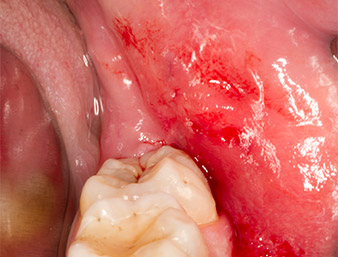

La ferita si è cicatrizzata senza complicazioni (Fig. 17) e le suture sono state rimosse dopo sette giorni. Il paziente ha segnalato il ritorno della normale sensibilità. Non si è più presentato alcun dolore.

Condizione dopo la rimozione delle suture

Fig. 17: Condizione dopo la rimozione delle suture 7 giorni dopo l'estrazione: la cicatrizzazione della ferita procede senza complicazioni. La parestesia, presente dopo l'osteotomia iniziale, è sparita, non è più presente dolore.